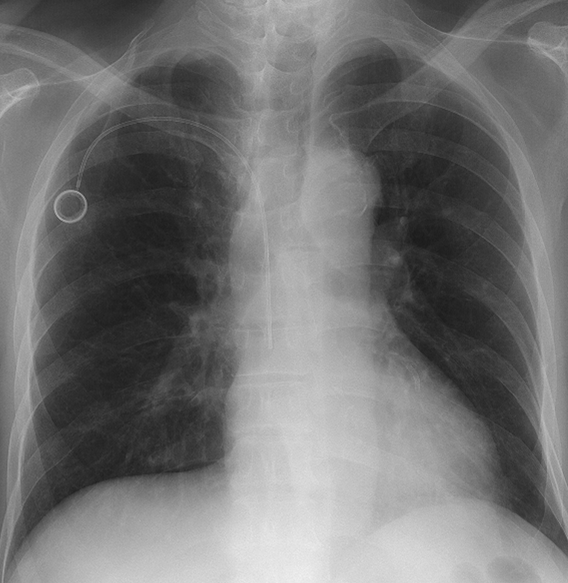

がん治療に欠かせない中心静脈ポート(CVポート)は、抗がん剤投与や点滴、採血をより安全かつ快適に行うための留置型デバイスです。当院では年間約900例のポート留置を行っており、すべて画像ガイド下で1530分ほどで実施しています。血管を正確に捉えることで合併症が少なく、患者さんの負担も軽減されます。点滴のたびに血管を探す必要がなくなり、治療の継続がよりスムーズになります。